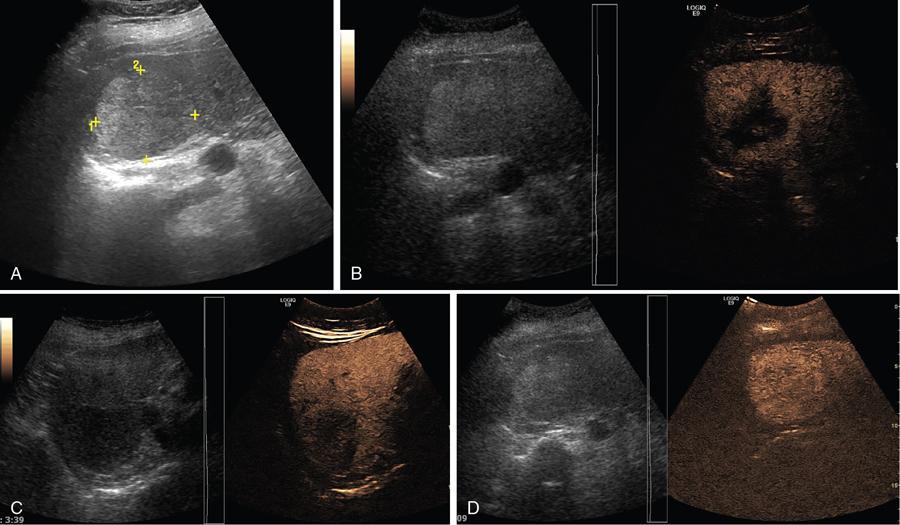

Samarjit Ghuman, Seema Sud, Deeksha Rastogi, Swapnil Sheth, T.B.S. Buxi PLAIN RADIOGRAPHY FOR HEPATOBILIARY IMAGING The diagnostic imaging techniques for hepatobiliary imaging can be intimidating with many techniques/modalities providing the information desired. The job of the diagnostic radiologist includes being familiar with the available choices and pick the ‘best fit’ keeping in mind the pros and cons of each modality, which includes plain X rays, Contrast studies using plain X rays and fluoroscopy, Ultrasound includiojng Doppler and Ultrasound elsastography, CT including multiphase CT and MRI and MRI elastography. Understanding the strengths and weaknesses of every modality as well as the ability to tailor each study individually will help to optimise patient cares. The abdominal radiograph is performed almost exclusively in the supine position and in the AP (anteroposterior) projection. In case of acute abdomen, an erect chest radiograph should also be performed to look for free air under the diaphragm. The standard abdominal radiograph should extend from the diaphragm to the inferior pubic rami, and includes the lateral abdominal wall musculature. Routinely no preparation is required for abdomen radiograph done for hepatobiliary imaging. The radiograph has limited soft-tissue contrast, however, the liver being the largest intra-abdominal organ, casts a perceptible shadow. The margins of the liver can indirectly be seen by outline of adjacent organs like lung, hemidiaphragm, pro-peritoneal fat line, kidney and gas shadows of stomach/colon. The right lobe is seen better than the left lobe of liver. The following pathologies may be visualized on the plain radiograph of the liver. Liver enlargement Liver mass Calcification Increased radiodensity of the liver Decreased radiodensity of the liver An ultrasound is the first line investigation; however, a radiograph may be done for routine evaluation of abdominal pain. The following pathologies may be seen on plain radiograph of the biliary tree. Calculi and Calcifications Gas ULTRASOUND OF HEPATOBILIARY SYSTEM Ultrasonography (USG) is the initial imaging modality of choice for scanning hepatobiliary system. USG is accurate and has high sensitivity and specificity in diagnosing biliary pathologies. Table 9.1.1 shows indications of ultrasound in hepatobiliary system. The real-time nature of ultrasound lends itself to demonstrate mobility of calculi and sludge and the sonographic Murphy sign can easily be elicited during scanning. The main disadvantage is operator dependence, patient’s body habitus, presence of gas which can obscure the visualization of organs, overlying bandages in a postoperative patient and incomplete evaluation in a nonfasting state. USG of upper abdomen should be done after 6–8 hours of overnight fasting. Milk and fatty food should be avoided as they cause contraction of the GB and may cause the GB walls to appear thickened. History of previous surgery, especially cholecystectomy should be elicited. The patient may be positioned in supine or left lateral decubitus position. The GB can be scanned from a high/lateral view, looking through the ribs in supine position or through a sub-costal view in left lateral decubitus position. Position of patient may be changed to demonstrate mobility of structures. The GB is an anechoic structure which is located in the GB fossa along the posterior and inferior aspect of the liver. It has a fundus, body and a neck. It should always be examined in at least two planes (Fig. 9.1.6A and B). The wall of the normal GB should measure 3 mm or less and pathological GB wall thickening can be due to cholecystitis or a neoplastic aetiology. Calculi appear as mobile hyperechoic foci, with distal acoustic shadowing. Other pathologies include polyps and sludge which can be differentiated on the basis of their mobility. The CBD measures less than 6 mm in diameter with increase in the diameter with patient’s age and after cholecystectomy. The CBD is usually scanned in an oblique subcostal plane with the patient in the left decubitus position (Fig. 9.1.7). Dilatation of the intrahepatic biliary radicles is readily assessed with USG and normal intrahepatic biliary radicles are usually not appreciated on USG. Ultrasound of the liver, broadly, is done to assess the size, surface (smooth, coarse or lobulated) parenchymal echogenicity (increased or decreased) vascularity and for presence and evaluation of intrahepatic masses or fluid collections. The liver is divided into right and left lobes by plane of middle hepatic vein which passes through GB fossa and notch of IVC (Cantlie Line). Couinauds classification is the most commonly used system for liver segmental anatomy and described liver into eight functional segments. It is based on distribution of portal and hepatic veins. Every segment has its branch from portal vein, hepatic artery and bile duct (Fig. 9.1.8). Curvilinear transducer (3–5 MHz) is used for routine examination of liver and GB (Fig. 9.1.9). A high-frequency linear transducer (9–11 MHz) (Fig. 9.1.10) can be used to look for subtle irregularity of the liver surface for early Cirrhosis and fine details of GB wall. The liver is scanned in deep inspiration, which causes inferior movement of liver, so that superior borders of the liver are well visualized. Supine position is used for the size of the liver. The measurement is made in sagittal mid clavicular position on right side, in craniocaudal dimension. It is taken from diaphragm to the lower end of the liver. It should be <16 cm and varies with age and sex. The liver is divided into four vertical sectors by three hepatic veins and plane of bifurcation of portal vein divides these 4 sectors in to 8 segments. The right hepatic vein creates vertical plane in the right lobe separating segments V and VIII (anterior) from VI and VII (posterior). The portal vein bifurcation creates a transverse plane and divides these segments into superior (VII, VIII) and inferior segments (V, VI). The left hepatic vein divides the left lobe into medial (IVa, IVb) and lateral sectors (II, III). The left portal vein divides left lobe into superior (Iva, II) and inferior segments (III, IVb). The middle hepatic vein separates medial segments of left lobe (IVa, IVb) from anterior segments of right lobe (V, VIII). Ligamentum teres separates segment III from IVb. Ligamentum venosum separates segment I from IV and II. Cystic duct is an anechoic tubular structure which connects neck of the GB to the extrahepatic biliary tree. In long axis view of GB, the neck of the GB is related to main lobar fissure which appears as a linear echogenic line which runs obliquely between neck of GB and right portal vein. In the right oblique sub coastal view CBD is seen anterior and parallel to portal vein. A series of standardized sections or views may be obtained for liver scanning. Transverse Subcostal View: In this view the probe is angled cephalic and placed transversely under the ribs on the right side and portions both lobes of the liver can be seen (Fig. 9.1.11). Mid Transverse View (Fig. 9.1.12) in this transducer is kept in transverse plane in the midline below the xiphisternum. It visualises the liver in an inferior to superior transverse oblique plane and portions of both lobes of liver can be seen along with right and left portal veins. This view is obtained by angling the transducer superiorly toward the hepatic venous confluence. In this view, we can see the three hepatic veins joining the IVC. Right Parasagittal View for Both Right Lobe and Kidney: This view allows assessment of inferior right lobe of liver. It also allows assessment of relative echogenicity of liver and renal cortex as both are seen together in the same image. Normal liver parenchymal echogenicity is greater than renal cortex and less that renal medulla (Fig. 9.1.14). Parasagittal Right MidClavicular View: In this transducer is kept in sagittal plane in right midclavicular line, and oriented supero-inferiorly. This is the standard view for assessing craniocaudal span of liver (Fig. 9.1.15). Parasagittal View for the Left Lobe: For evaluation of left lobe of liver and lateral segments (2 and 3) (Fig. 9.1.16). This view is obtained along the direction of the main portal vein. CEUS of the liver is done to evaluate Focal Liver Lesions and complements traditional B mode ultrasound and Doppler study. It is a simple, accurate and cost-effective tool complimenting indeterminate CT and MRI findings or for characterization of lesions in patients who cannot receive CT/MRI contrast and can be used in patients with compromised renal function, with minuscule risk of side effects. As CEUS is real-time, microvasculature can be studied along with tissue perfusion kinetics. Indications and uses of CEUS: Contrast agents and technique: Interpretation: Contrast-enhanced ultrasound of a hepatic hemangioma in different phases (Fig. 9.1.19). Limitations of CEUS: Liver elastography is a noninvasive method for diagnosing liver fibrosis. Liver fibrosis is induced by chronic liver disease leading to cirrhosis and liver cancer. Liver biopsy is the gold standard for diagnosing the degree of fibrosis and for staging but it is an invasive method. Elastography helps in analysing the elasticity or the stiffness of the tissue. A stiffer liver tissue indicates fibrosis or chronic liver disease. ARFI is based on the principle of measuring Shear wave velocity. Short duration acoustic pulses which are generated in the tissue and these give rise to shear waves which travel, perpendicular to the ultrasound beam. These shear waves cause tissue displacement followed by recovery. This displacement and recovery depend on tissue stiffness. To monitor these shear waves US beams of low intensity are emitted continuously parallel to the main beam along with the push pulses, and these beams can gather data regarding the tissue stiffness. The shear waves cause tissue displacement and this tissue then recovers from the impulse. From this data the degree of tissue stiffness can be obtained which is displayed either as a map or quantitatively where tissue elasticity is expressed as shear wave velocity measured in meters per second. F0, normal; F1, enlarged fibrotic portal tract; F2, periportal/initial porto-portal septa with intact architecture; F3, architectural distortion with no obvious cirrhosis; F4, cirrhosis. It is also known as Transient Elastography (TE) and works on the similar principle as ARFI, the difference being that B mode ultrasound image is not produced. DOPPLER OF PORTAL VEIN The portal vein divides at the portahepatis into right and left branches. The right portal vein divides into anterior and posterior branches, and the left portal vein divides into medial and lateral branches. Portal vein shows a continuous, forward low-velocity flow (15–28 cm/s) on colour Doppler scanning. The flow is hepatopetal, that is, towards liver and is red in colour as it is flowing towards the transducer. It has an undulating pattern and shows respiratory variation with increase flow in inspiration. It may reflect cardiac variation and shows postprandial increase calibre and flow in healthy individuals. Normal Doppler waveform of portal vein (Fig. 9.1.22). Portal hypertension can be defined as elevated pressure within the portal venous system resulting in impaired blood flow through the liver. INTRAOPERATIVE PANCREATIC AND HEPATIC ULTRASOUND Intraoperative ultrasonography of the pancreas was first described in 1980 by Lane and Glazer. It is an important technique for guidance of both open and laparoscopic surgical procedures of the pancreas. As the transducer is in direct contact with the organ of interest, with no interference with air of adjacent soft tissue, it provides good resolution. It is considered superior to CT and MRI in assessing the intraoperative tumour resectability and vascular invasion and guiding resection. Indications and uses For intraoperative US during open surgical procedures, a high-frequency linear-array transducer or the hockey stick transducer (Fig. 9.1.23) are used which create high-resolution detail of the exposed pancreas. The side-fire curved linear-array transducer is effective for obtaining a wider view of the pancreas and its surrounding structures and for scanning the liver. Intraoperative hepatic ultrasound gives the real-time visualization of the hepatic anatomy and aid for surgical planning and making decision during surgery. Indications and uses Transducer and technique Limitations MULTIDETECTOR CT OF THE HEPATOBILIARY SYSTEM AND CHOLANGIOGRAPHY The cross-sectional plane of the patient is denoted as the x/y plane. The plane along which the table moves is the ‘z’ plane. Multidetector CT denotes more than one detector along the Z-axis, with the latest machines having up to 320 and now even 640 rows of detectors. This provides CT with very fast, high resolution, isotropic images which can be reconstructed in any plane or even curved planes. MDCT scanners can comfortably scan the entire abdomen in 10 seconds or less, thereby allowing visualization of different phases of contrast enhancement. Contrast Media (CM) after administration gets distributed from the intravascular compartment into the interstitial spaces. Intravascular arterial enhancement (for angiography) and parenchymal enhancement have different kinetics. Parenchymal enhancement is directly proportional to total iodine dose being administered and inversely proportional to weight, which is a marker of extracellular volume into which contrast redistributes. Rate of iodine administration has no effect on degree of parenchymal enhancement. As a general rule approx. 500–600 mg of iodine/kg body weight achieves adequate hepatic parenchymal enhancement. For a 60 kg adult, this translates into approx. 100–120 mL of contrast containing 300 mg of iodine per mL. Intravascular or arterial enhancement is controlled by rate at which iodine is administered (flow rate and iodine concentration of CM) iodine flux and duration for which contrast is administered longer injection also leads to better overall arterial opacification due to recirculation effects. This principle is made use of while performing abdominal CT Angiography. Higher iodine delivery rate per unit time using a higher iodine concentration contrast medium also improves conspicuity of vessels and hypervascular lesions such as HCC. For identical parameters, difference in arterial enhancement between patients is dependent on cardiac output with enhancement being inversely proportional to cardiac output. For optimal imaging and enhancement, in multiphase imaging and angiographic studies, contrast material administration and parenchymal or vascular enhancement must be synchronized with CT data acquisition. The two main methods are: Test bolus technique: A test dose of contrast is given and the time to peak enhancement is measured in a ROI placed in a target vessel this information can be used to tailor CT acquisition. Automated bolus Triggering: ROI is placed in target vessel (usually aorta at level of diaphragm) on a plain image. While CM is injected, a series of low dose scans is obtained through the ROI. When the density of contrast reaches a predefined threshold (e.g. 150 HU), at time ‘t’ the scan is automatically triggered. The trigger delay after time ‘t’ is a minimum of 2 sec, and can be programmed to any value. Bolus tracking is nowadays the method of choice for planning contrast medium administration and this technique provides more homogenous opacification. Saline chase is recommended in all multiphase protocols. Significant amount of contrast may be present in the peripheral veins after injection of IV contrast and use of saline chaser leads to better vascular enhancement and lower overall contrast dose (Fig. 9.1.24). Using the above, a standard sequence of acquisitions and contrast enhancement techniques can be tailored to the pathology and organ of interest and pre-programmed into the scanner menu, which includes kVp, mAs, pitch, rotation time, slice thickness etc. This is known as a scan protocol. However, these can be modified as necessary. For example, rotation time can be shortened and pitch can be increased for breathless patients to reduce scan times (Table 9.1.4). Multidetector CT is the workhorse of hepatobiliary imaging. It plays a major role in imaging congenital, traumatic, infective, neoplastic and vascular pathologies of the hepatobiliary system. Scans can be obtained with or without intravenous (IV) iodinated contrast material administration. Multidetector CT scanners are capable of imaging multiple phases at different points of time following injection of contrast and provide dynamic imaging due to fast scan times and rapid coverage of the abdomen. Indications for liver imaging include, but are not limited to: Unenhanced Scan: Hepatic fat estimation, radio opaque biliary calculi. Single Phase Scans: Liver abscess, polytrauma, follow up of known oncologic or benign lesions, abdominal pain, suspected cholecystitis. Multiphase Studies: Evaluation of hepatic masses, imaging in cirrhosis, imaging for resectability, liver donor evaluation, malignancy of GB, hepatic venous outflow obstruction etc. CT Angiography of Hepatic Vessels: Trauma, vasculitis, post-operative bleeding and as a part of multiphase studies. Depending on the indication, scanning protocols can be tailored to highlight the suspected pathology and provide relevant answers for further management (Table 9.1.5). The liver has a dual blood supply, most of which is derived from the portal vein. After injection of contrast, until the portal vein provides recirculated contrast material filled blood to enhance the hepatic parenchyma, the hepatic parenchymal enhancement is relatively poor and dependent only on the hepatic artery. The hepatic arterial phase can be divided into an early arterial phase without any portal opacification, a late arterial or portal inflow phase in which there is some portal vein opacification. This is followed by a portal venous phase in which portal and hepatic veins are enhanced (also called the hepatic venous phase in some articles). In addition, an unenhanced/plain scan and an equilibrium phase can also be acquired. Tumour conspicuity of hypervascular lesions was found to be best on the late arterial or portal inflow phase (Fig. 9.1.25). The early arterial phase is seen up to 10 seconds after trigger, and provides ‘angiographic’ images of hepatic arterial anatomy. This phase is used to provide details regarding arterial anatomy and morphology. Later arterial phase 18–23 seconds, portal venous phase 60–70 seconds and equilibrium phase 180 seconds are obtained after trigger. Equilibrium phase images have been shown to increase detection of hepatocellular carcinoma in cirrhotic patients. The portal venous phase is the standard phase for routine chest/abdomen survey and follow up of hepatic abscesses and hypovascular metastases. Single Phase Scan Protocol: Oncologic follow-up, Liver Abscess – For routine single-phase CT, contrast as per body weight can be injected over 40 seconds and scanning can be done after an empiric delay of 70 seconds from the beginning of injection. This protocol provides good parenchymal enhancement and portal and hepatic vein visualization. Plain scan is optional. Dual-Phase Scan Protocol: Hepatic evaluation in patients with malignancies known to have hypervascular metastases – Neuroendocrine tumours, renal cell carcinoma, thyroid carcinoma, (.) melanoma etc. Late arterial Phase 20–22 seconds and Portal venous phase at 60–70. Plain scan optional. Hepatic Resection Protocol: For patients with known hepatic mass being evaluated for resection. Early arterial phase provides pure arterial or angiographic images. It is obtained at 8–10 seconds post trigger followed by portal venous phase at 60–70 seconds. This is required for arterial and venous anatomy and volumetric evaluation if required. Plain scan is not required. In case a hepatic mass needs characterization as well as resectability planning, late arterial and equilibrium scans may also be done. Indications for angiography are further discussed in the section on angiography. The same biphasic protocol using angiography or arterial phase images is used in patients with trauma suspected to have pseudoaneurysms, hepatic artery thrombosis or dissection in transplant recipients, evaluation of living donors and in patients in whom an angiographic ‘road map’ is required prior to intervention. Triphasic or 4 phase scan Protocol: Standard of care for patients with cirrhosis being evaluated for Hepatocellular carcinoma and for patients being evaluated for hepatic mass of uncertain aetiology. Late arterial phase scan: 20–22 seconds, Portal venous scan at 60–70 seconds and Equilibrium scan at 180 seconds. Plains scans are optional. Our institutional practice is to always do plain scans in patients who have undergone hepatic intervention. Plain scans also help to visualize siderotic and steatotic nodules. A further delayed scan is suggested by some authors at 10–15 minutes for characterization of hepatic masses of uncertain provenance. This is particularly useful in cholangiocarcinoma (Table 9.1.6).

Contrast-enhanced ultrasound (CEUS)

Phase

Post Injection Time in Seconds

End Time

Arterial

10–20

25–35

Portal venous

30–45

120

Delayed phase

>120

Microbubble disappearance (240–360)